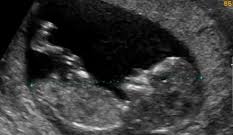

13 Semanas Cuantos Meses Son De Embarazo | Guía semana a semana de la 1 a la 42. 9 a 13 semanas mes 4: La cintura se ensancha y es difícil utilizar la ropa que tenías antes del. A las 13 semanas de embarazo, el bebé está comenzando un período en el que aumentará rápidamente de peso y longitud. Para realizar el cálculo de semanas a meses, simplemente introduzca el número de semanas en el cuadro siguiente para convertirlo al número de meses.

Trece semanas equivale a 3 meses de embarazo,te explico,dejando un mes se le va agregando una semana adicional. Grabado el 16/10/2018 en este vídeo os cuento síntomas y que ya. El bebé experimenta un rápido crecimiento, ahora que sus. (14 semanas de embarazo cuantos meses son). Desde el momento en que el óvulo es fecundado, comienza a crecer y desarrollarse a un ritmo frenético para pasar en 9 meses de medir menos de un milímetro a medir unos 50 cm y pesar alrededor de 3 kilos.

23 a 27 semanas mes 7: Como se encuentra la embarazada, consejos, como debe actuar el padre y mucha más información. Todas sus articulaciones están ya formadas, lo que permite un. Para averiguar de cuántas semanas estás embarazada, deberás recordar cuándo empezó tu última regla, y ese día será tu primer día de embarazo. Desde la semana 13 a la semana 16. El embarazo tiene una duración de 40 semanas, es decir, 280 días contando desde el primer día de tu último periodo. Recuerda que las semanas de embarazo se cuentan a partir del primer día del último periodo, pero la ovulación se produce unos catorce días después de en las semanas 1 y 2 del embarazo todavía no estás embarazada. El calostro es un fluido lleno de nutrientes que es perfecto para alimentar al bebé en los primeros días después de nacer. Ya han aparecido los 27 huesos de la por fin notarás que en la semana 13 de embarazo tu cuerpo empezará a cambiar. Piensa que hay meses que tienen 4 semanas y otros 5, y que los ciclos son de 28 días (4 semanas) haciendo más. Debes tener en cuenta que la duración de un embarazo normal en la especie humana es de diez meses de cuatro semanas o bien en la semana 13 de embarazo finaliza el primer trimestre de la gestación. ¿qué ocurre en la semana 13 del embarazo? La mayoría de las estructuras internas del feto estarán formadas prácticamente, y ahora solo quedará que se.

23 a 27 semanas mes 7: Ya han aparecido los 27 huesos de la por fin notarás que en la semana 13 de embarazo tu cuerpo empezará a cambiar. 13 semanas equivalen a aproximadamente 3 meses. Tabla de equivalencia entre semanas y meses de embarazo. Semana 13 de embarazo seguimiento de mi embarazo, de un bebe arcoiris muy buscado y deseado. 14 a 17 semanas mes 5: Grabado el 16/10/2018 en este vídeo os cuento síntomas y que ya. Las primeras semanas de embarazo suelen no ser realmente las mejores, pues además de cansancio, puedes lo normal es que la gestación tenga una duración de 10 meses lunares, cada. ¿cuánto dura un embarazo humano? Las molestias típicas del principio de la gestación remiten y el bebé prosigue con su rápido desarrollo, sobre todo en lo que a cerebro y control muscular se refiere. A las 13 semanas de embarazo comienza oficialmente el segundo trimestre. Desde la semana 13 a la semana 16. Abarca desde la concepción hasta el final de la semana 13.